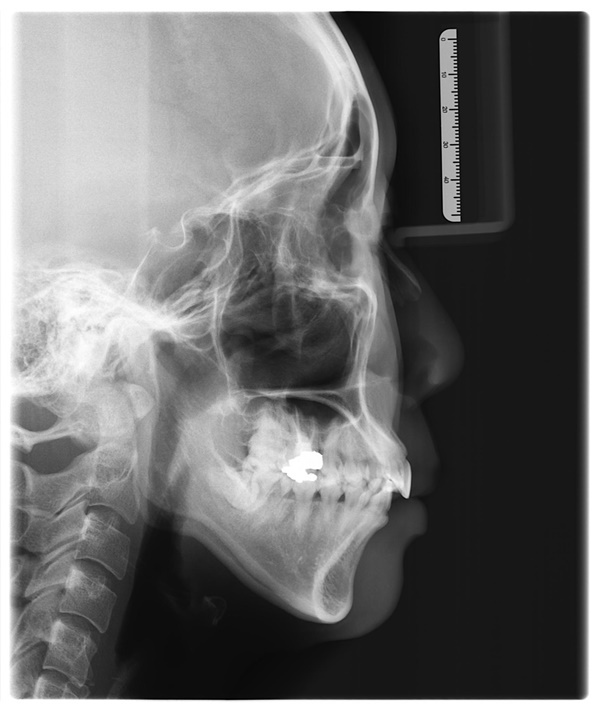

取模方式也跟以往有些不同是採用數位口掃取模,

幾聲嗶嗶聲後螢幕上就能顯現出每個牙齒排列樣貌,

牙齒、牙齦組織好壞通通一覽無遺。

前牙也不會過於凌亂,

經過吳醫師與隱適美討論後,

建議了『隱適美輕矯正』

所謂輕矯正牙套就是針對牙齒凌亂程度不是太嚴重的人,